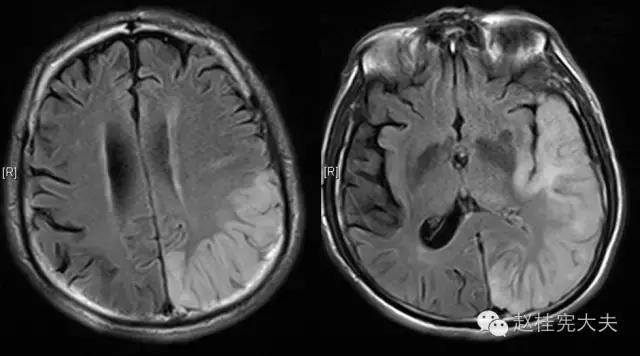

患者的磁共振影像不符合脑血管病的血供分布,跨了大脑中动脉和大脑后动脉范围,且病灶偏皮层分布。大脑前、中、后动脉血供分布(横断面)见下图

这不是一个真的“脑卒中”,而是一个“卒中样发作”。

似乎,一切该有的,都有了,诊断来了个大逆转,线粒体脑肌病伴乳酸血症和卒中样发作(MELAS)的诊断呼之欲出了,患者此次卒中只是本病中枢神经系统损害的表现......